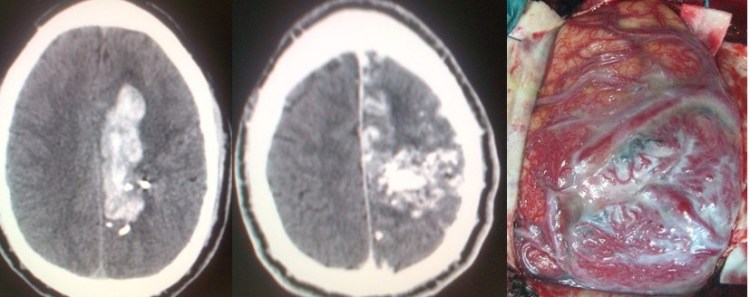

- Malformaciones arteriovenosas (MAVs): Responsables de un 4-5% de las hemorragias subaracnoideas. Están representadas fundamentalmente por las MAV piales, caracterizadas por la presencia de ramas arteriales que dan lugar a un nido malformativo, compuesto por arteriolas y capilares aberrantes, que recibe sangre a alta presión y que drena a través de una o varias venas. Por lo general, se trata de lesiones complejas cuyo tratamiento va a estar condicionado por su tamaño, localización dentro del cerebro y características del drenaje venoso. En caso de que se diagnostiquen previo a su ruptura (generalmente debido a que pueden inducir crisis epilépticas) y midan menos de 3 centímetros, pueden ser tratadas con radiocirugía, si bien en estos casos el efecto del tratamiento se demora unos 2 años. La cirugía por su parte constituye el tratamiento estándar de estas lesiones. Puede tener lugar, al igual que los aneurismas, de forma previa a la ruptura o bien tras producirse ésta. Previo a la cirugía debe considerarse la posibilidad de la embolización de la lesión.